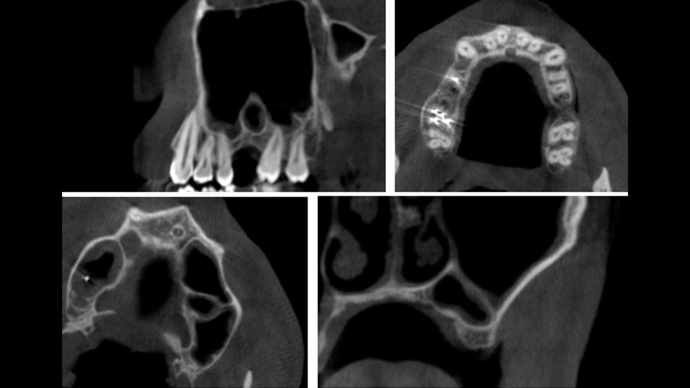

Clinical case: Installation of dental implants in complicated anatomic conditions using crest lifting methods

- Courtesy of Dr.Alexander Lysov, Russia -

Keywords

AnyRidge, complicated anatomic conditions, crest lift, MICA Kit, Dr. Alexander Lysov, bone regeneration, GBR, #26, maxillary posterior

Products:

AnyRidge implant system, MICA Kit